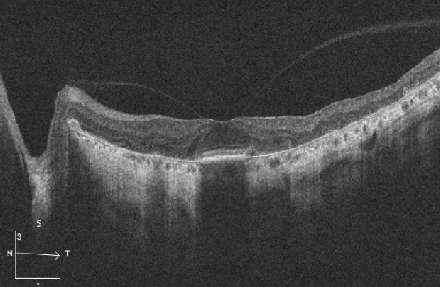

High Definition Images: HD 5 Line Raster

ü Imagen D y E: Lesión coroidea que levanta la macula, asociada a líquido subretinal